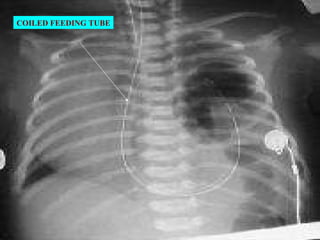

INV:   X ray chest: bowel loops in the chest Mediastinal shift with Ryles tube in situ showing the tip. X ray abdomen : Abdomen-relatively devoid of gas. Prenatal sonography : Bowel loops in the chest. CT& MRI : Defect in the diaphragm compressed fetal lung intestinal loops in the thorax. ABG : pH:7.2 paCO 2 >40mmHg paO 2 >60mmHg CONGENITAL DIAPHRAGMATIC HERNIA

COILED FEEDING TUBE